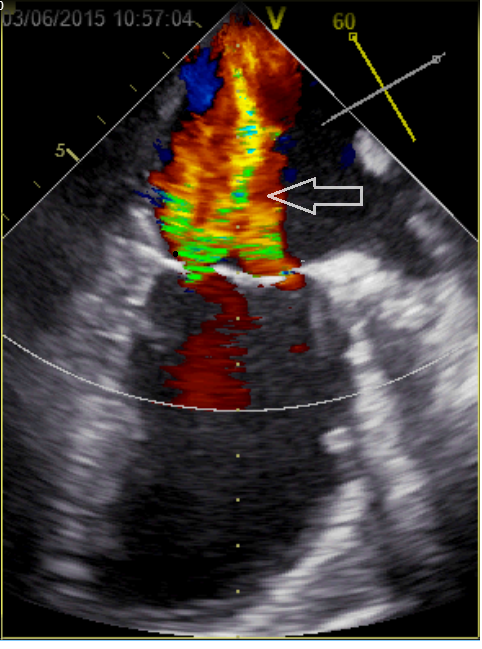

Video 1b – Slokdarmechocardiografie vóór mitraclipbehandeling, 2-kamer opname linkerventrikel. Met color doppler is de ernstige insufficiëntie zichtbaar

Figuur C – Slokdarmechocardiografie, 2-kamer opname linkerventrikel. De pijl geeft de (ernstige) mitralisklepinsufficiëntie aan.